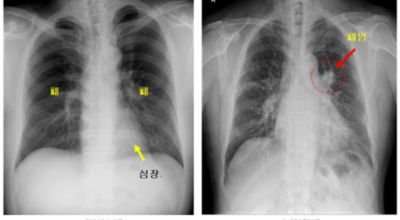

폐암 검사는 X-ray를 통해서 검사하는데 , 크기가 작거나 구석에 위치한 경우 확인이 어려운 경우도 있습니다. 그리고 조직 검사를 통해서 정확한 진단을 하게 돼요. 폐암이 발견되면 종양의 크기나 전이 여부 , 위치에 따라서 수술 여부를 결정하게 되어요.